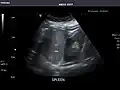

Spleen

Spleen: Normal in size.